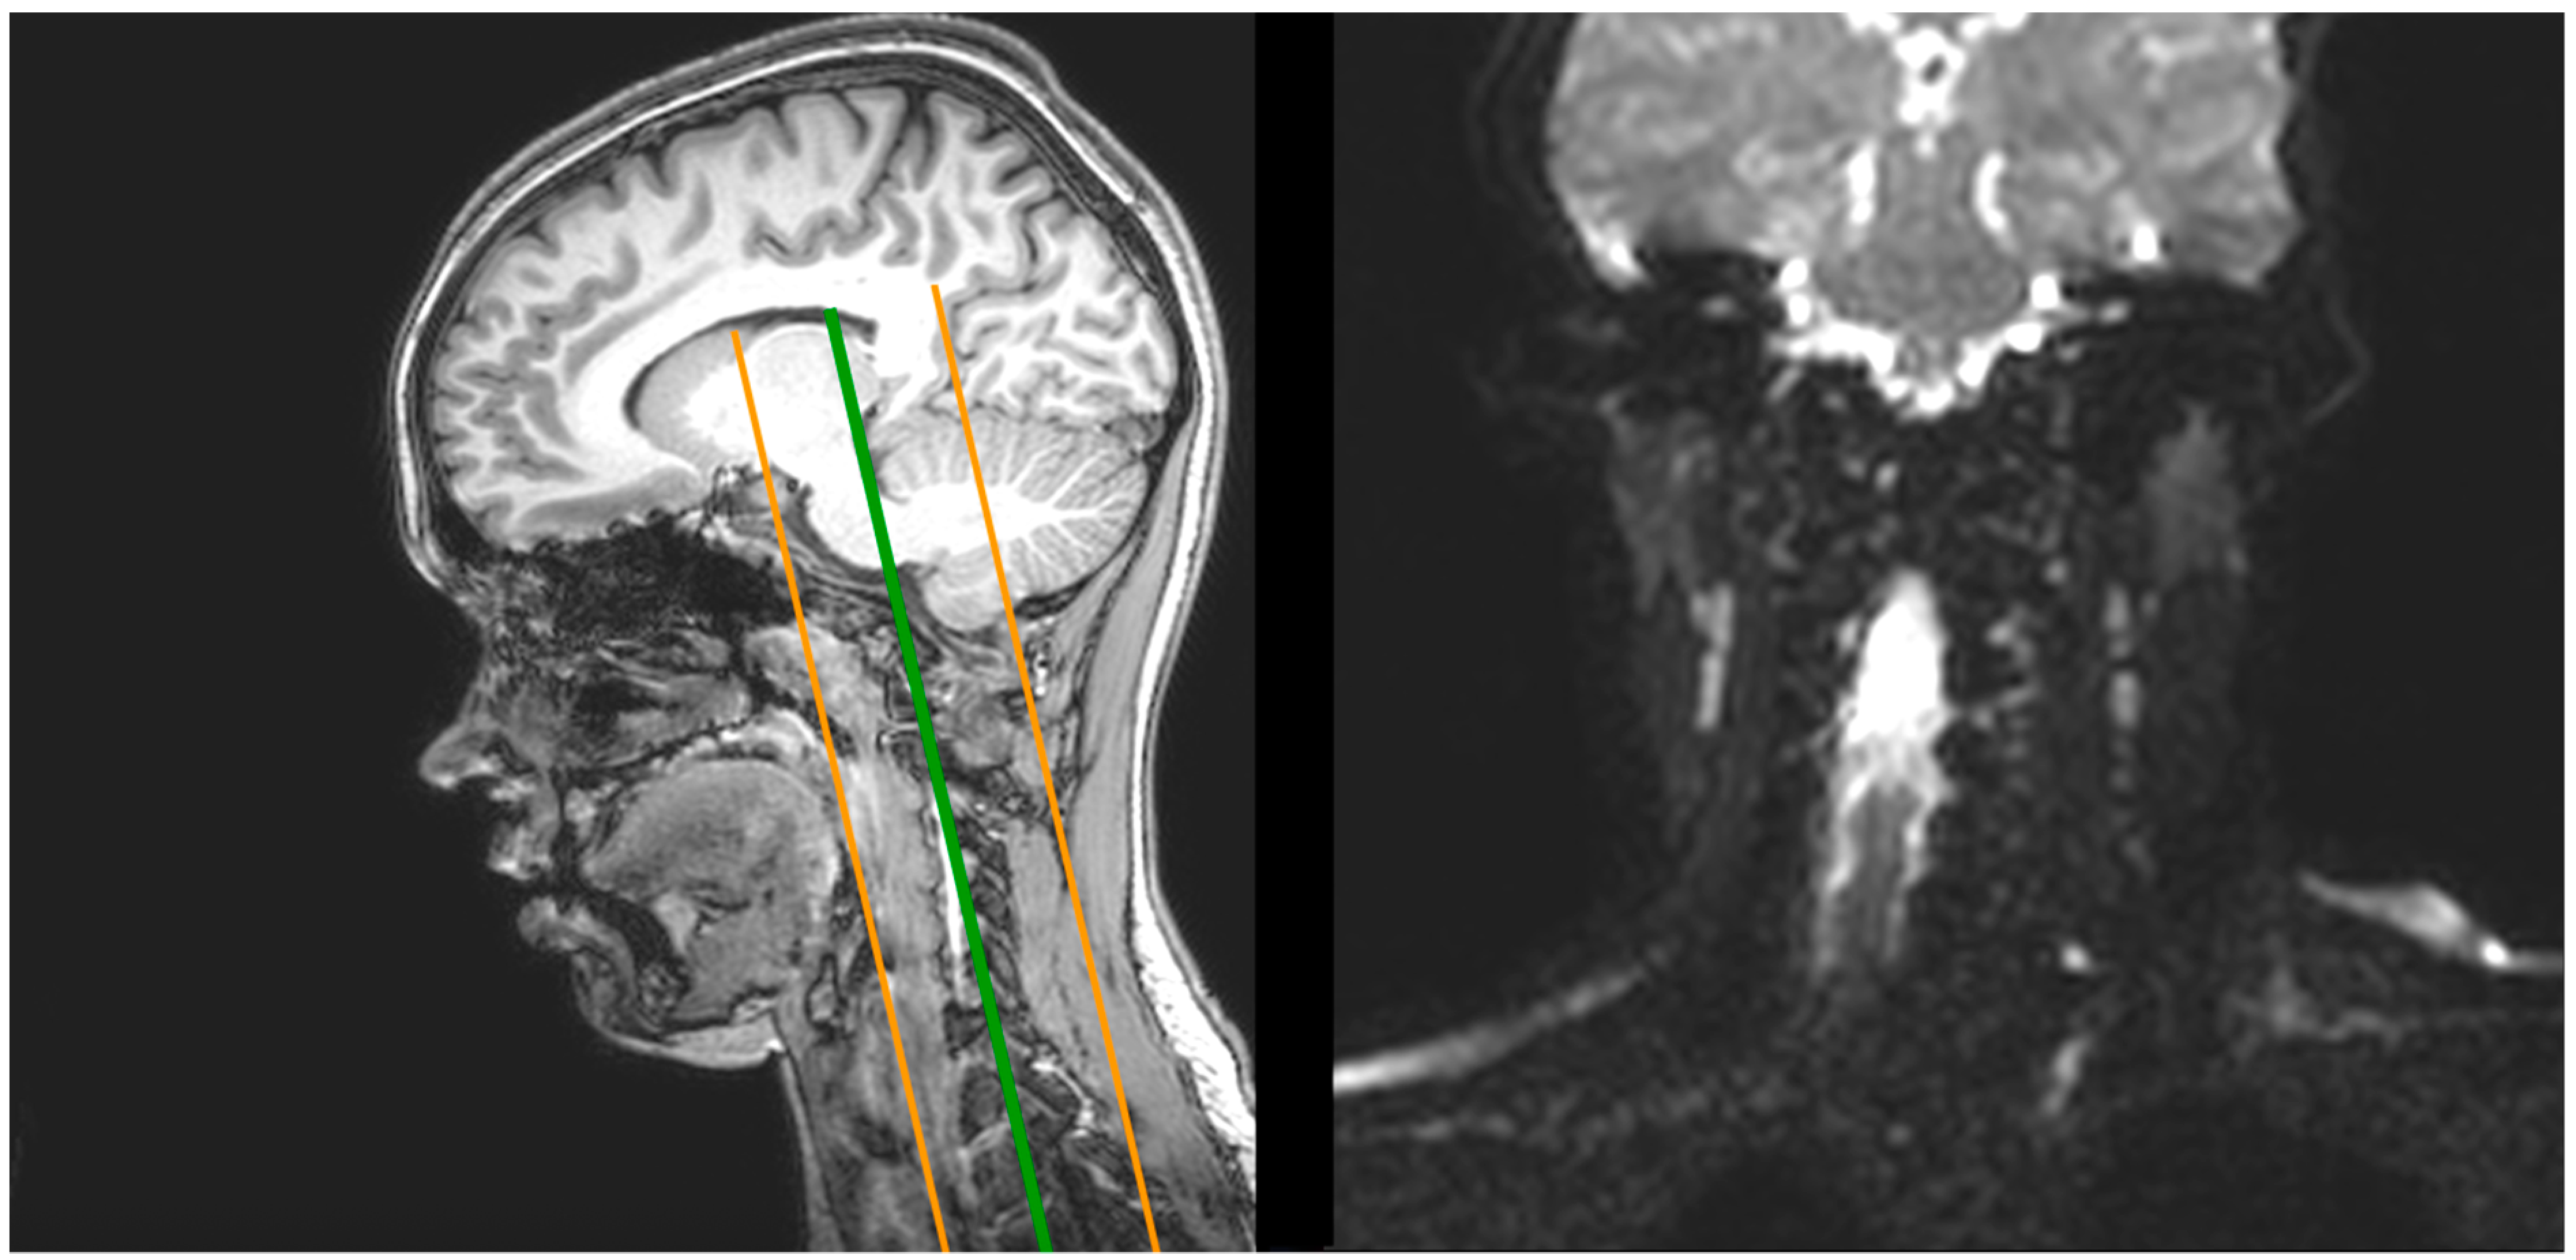

2.1. Magnetic Resonance Imaging (MRI)

2.1.1. Image Processing